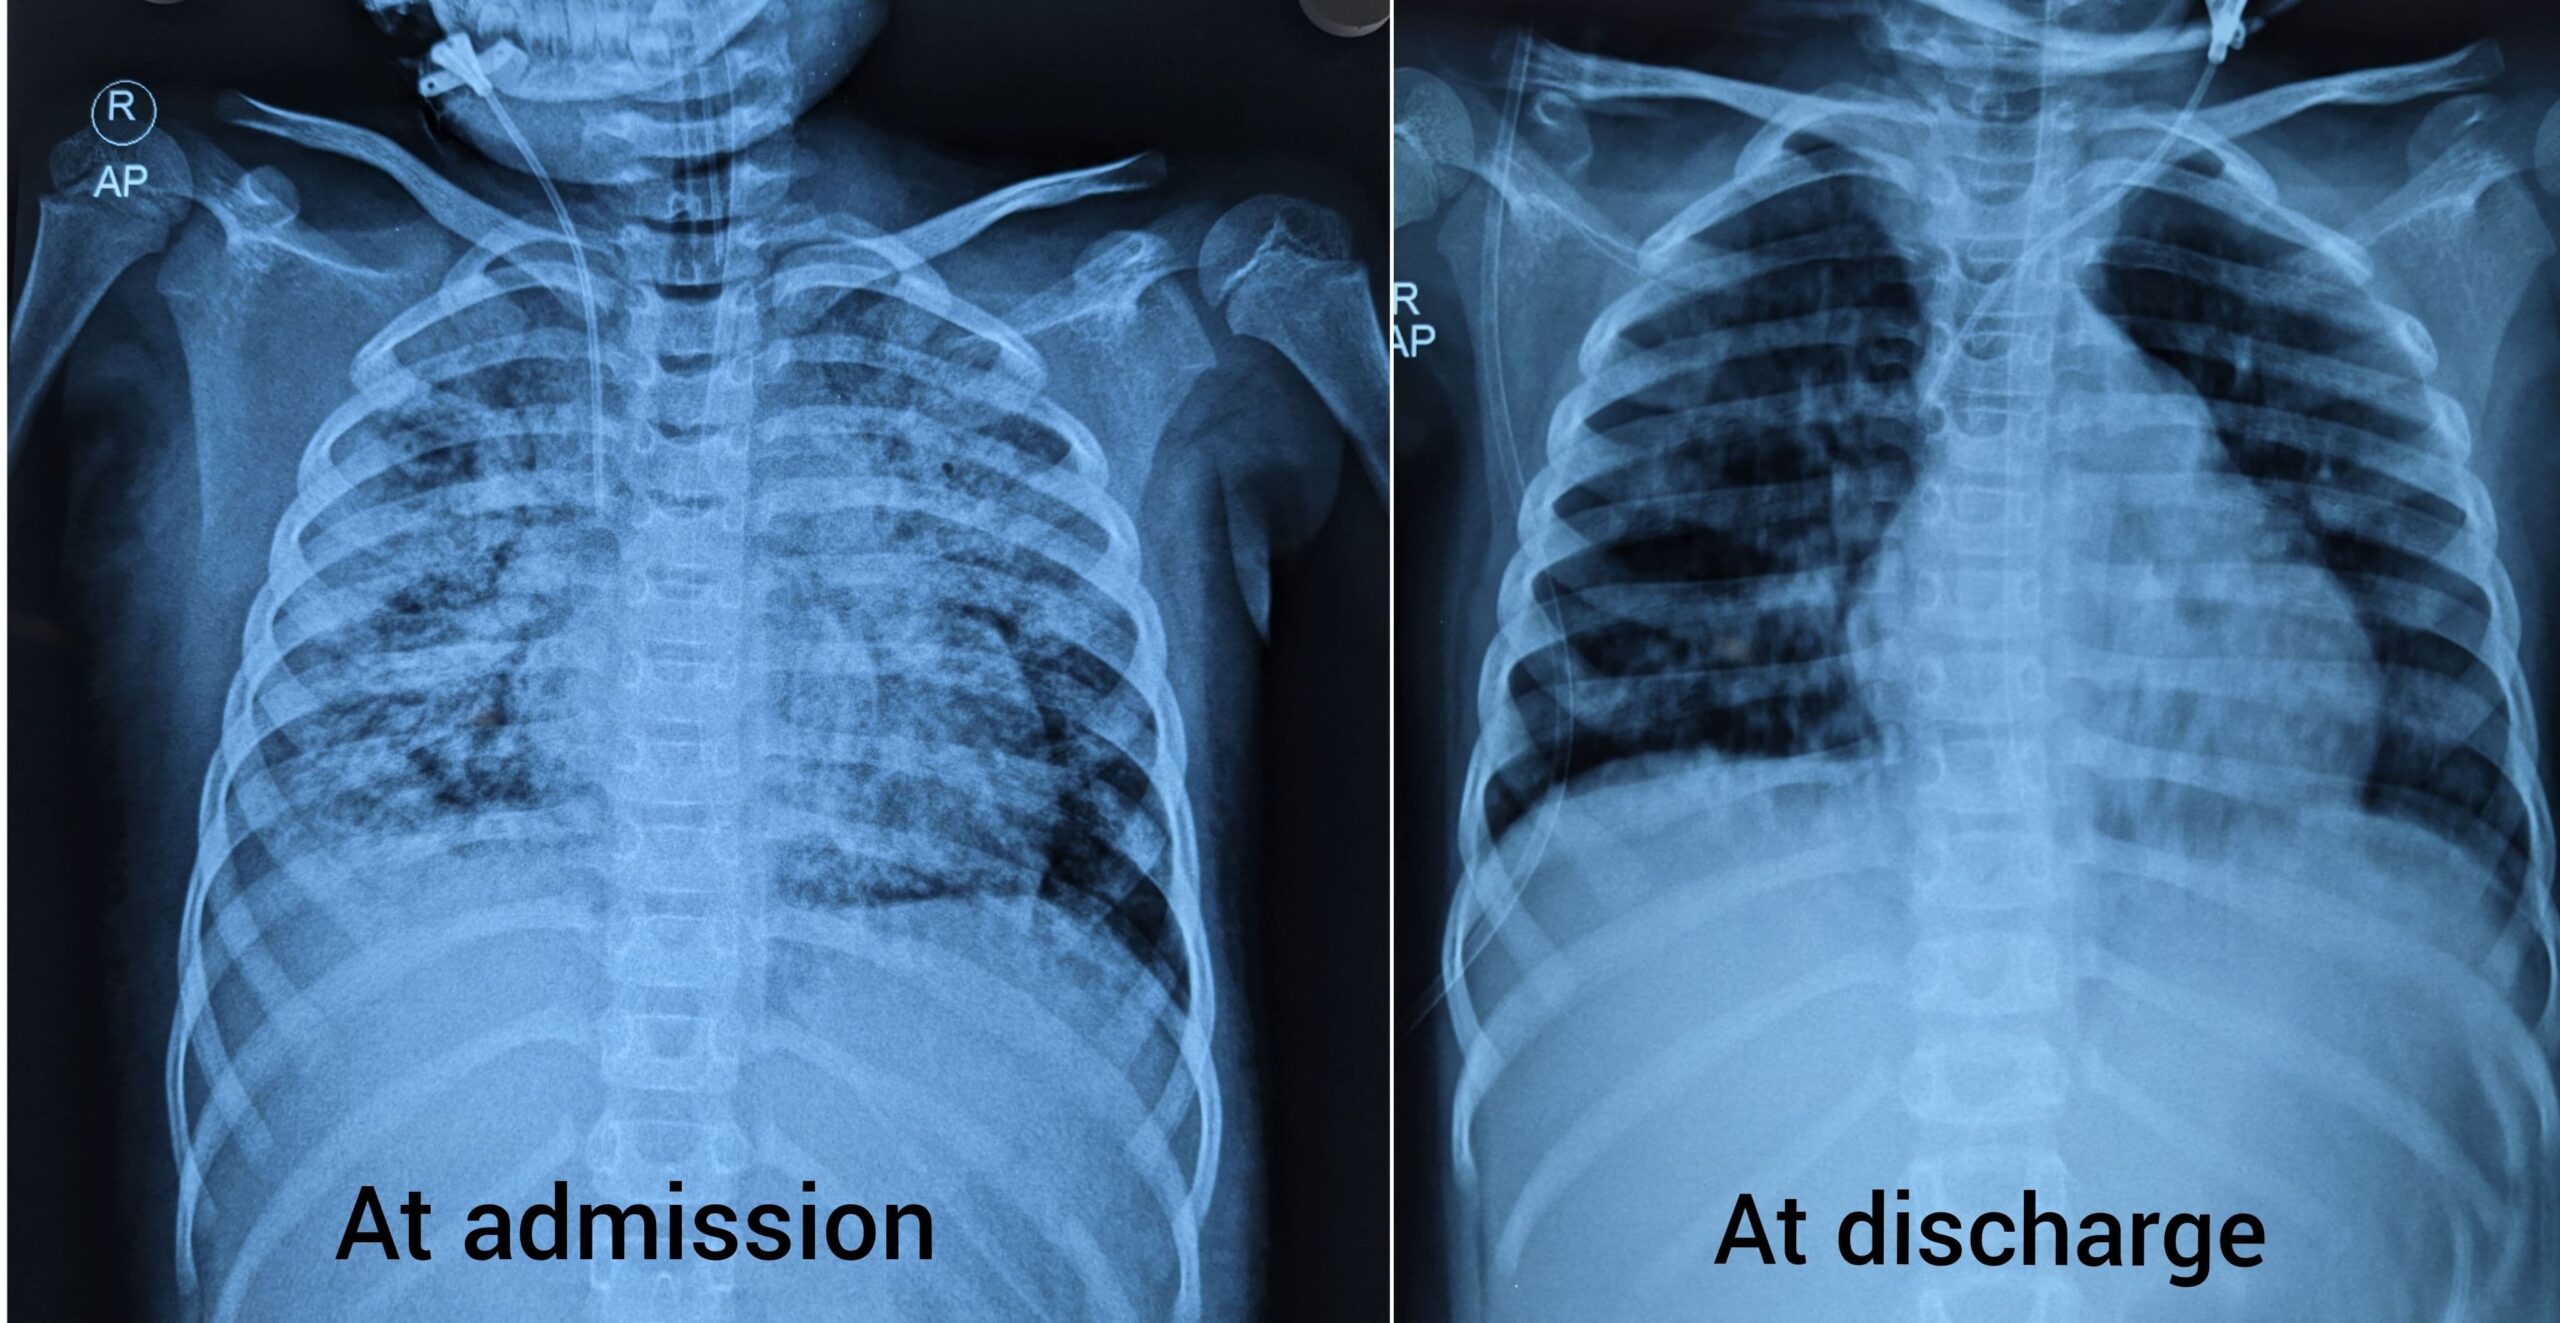

Story of a fighter brave heart!! A courageous 3-year-old boy was referred to Ankura Hospital...